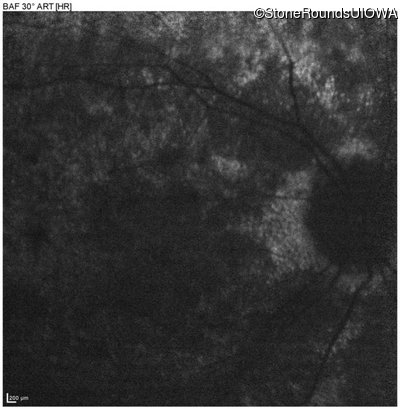

Diagnosis & molecular findings

Disease Gene Allele 1 variant(s) Allele 2 variant(s) Inheritance mode

AR Stargardt Disease ABCA4 IVS38-10T>C IVS38-10T>C AR

Gene:

Allele 1:

IVS38-10T>C

Allele 2:

Inheritance:

AR